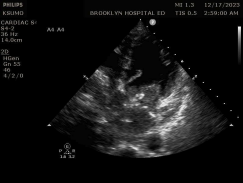

CaseReport_Biatrial Myxoma_Fig2